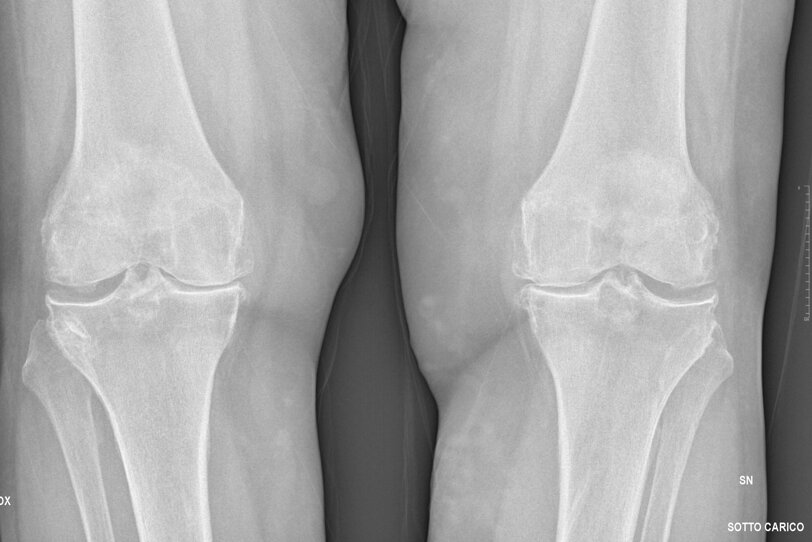

La diagnosi è prevalentemente clinica, raccolta una esaustiva anamnesi e dopo un completo esame obiettivo. Per valutare il danno articolare e quindi poter stadiare l’artrosi, vengono eseguite dal paziente delle radiografie del ginocchio, in due proiezioni, possibilmente sotto carico, in modo da poter valutare l'allineamento dell'arto e completare il planning pre-operatorio. Radiograficamente l’artrosi si caratterizza da: restringimento della rima articolare, osteosclerosi, presenza di osteofiti e geodi.